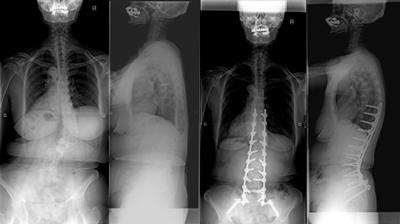

骨切りを併用した後方矯正固定術

せぼねの変形が大きかったり、再手術の場合には癒合してせぼねの骨切りを行い、再度矯正固定を行う場合があります。5時間前後の長時間の手術となります。入院期間は小児患者様で2週間程度、大人の患者様では3週間程度で場合によってはリハビリテーション病院へ転院をして頂き、さらにリハビリテーションを行います。

-

腰椎固定術後後弯に対する椎体骨切り術を併用した後方矯正固定術